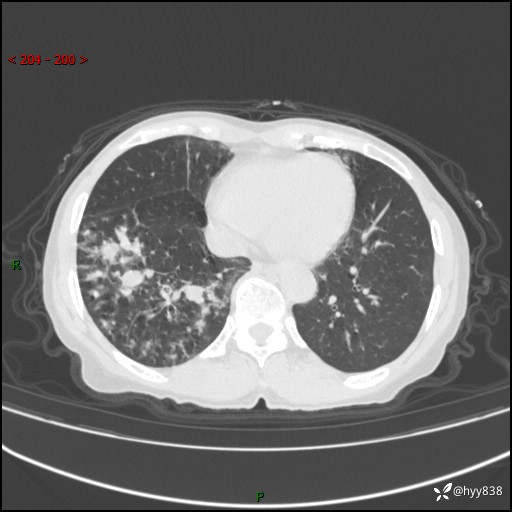

患者性别:男

患者年龄:69岁

简要病史:咳嗽咳痰2月,夜间加重

临床诊断:感染

胸部CT平扫